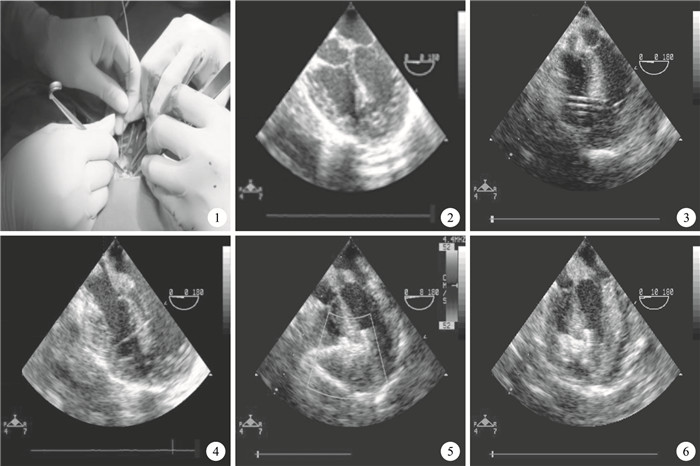

所有患兒靜脈吸入復合全身麻醉,氣管內插管,常規放置食管探頭,根據患兒大小將探頭放置至合適的深度。食管彩色超聲心動圖(Philips iE33超聲診斷儀,探頭頻率3~5 mHz)檢查再次明確伴發的心臟畸形類型及肌部室間隔缺損的位置、大小和室間隔厚度。術中患兒取平臥位,做胸骨下段正中切口,長度3~5 cm,劈開胸骨下端,縱行切開心包下部,食指輕壓右心室前壁表面,避開冠狀動脈(圖 1),在經食管超聲心動圖(TEE)指引下選擇與室間隔缺損角度最小、距離最近點為穿刺點(離室間隔缺損垂直距離最近處),取5-0 Prolene線作“U”形荷包,此時TEE仔細觀察缺損位置(圖 2),盡量將荷包縫線位置選擇在正對室間隔缺損處,以使鞘管能盡量垂直穿過室間隔(圖 3)。然后選擇合適的穿刺針,于TEE引導下導入引導鋼絲,鋼絲直頭端進入右心室腔,將其穿過室間隔缺損進入左心室腔(圖 4)。建立起輸送軌道。然后在TEE實時監測下推送封堵器。要反復進行推拉試驗,如果無移位,無殘余分流和心瓣膜反流,心律正常,即可釋放封堵器,撤出輸送裝置。仔細定位主動脈瓣及二尖瓣、三尖瓣,避免損傷。再釋放封堵器腰部和右盤面,使右盤面緊貼室間隔右心室面,在TEE監測下作反復推拉試驗,確認封堵器位置固定無誤。再繼續監測15 min,以防封堵器脫落及其他并發癥發生(圖 5)。

39例中有3例患兒(7.7%) TEE診斷不適宜行封堵治療,其中1例由于右心室流出道有異常肌束,2例由于邊緣過短不適宜行封堵手術,而改為體外循環下心內直視手術,患兒均在4 h內拔除氣管內插管,術后3~4 d出院。術后常規口服阿司匹林5 mg/(kg?d)6個月,36例患兒隨訪6個月以上,TTE顯示無封堵器脫落、移位,無溶血和房室傳導阻滯,人工瓣膜表面光滑,無異物(圖 6)。心臟明顯縮小,心功能正常,無神經系統并發癥發生。其中3例術后存在輕微的殘余分流,隨訪6個月均消失。